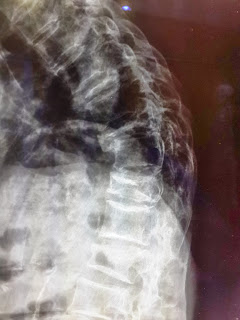

ภาพของผู้ป่วยที่มีหลังโก่งเนื่องจากมีการยุบตัวของกระดูกสันหลัง

นอกจากหลังโก่ง ผู้ป่วยยังมีอาการปวดหลัง ร่วมกับอาการปวดร้าวลงขา ลงน่องและชาบริเวณหลังเท้าร่วมด้วย

ภาพรังสีแสดงการยุบของกระดูกสันหลังหลายระดับ วิธีการดู คือ จะสังเกตจากความสูงของกระดูกสันหลังเทียบกันในแต่ละระดับ จะพบว่าส่วนของกระดูกสันหลังที่ยุบลงนั้นจะมีความสูง

ของกระดูกสันหลังลดลงเมื่อเทียบกับกระดูกสันหลังที่อยู่ติดกัน